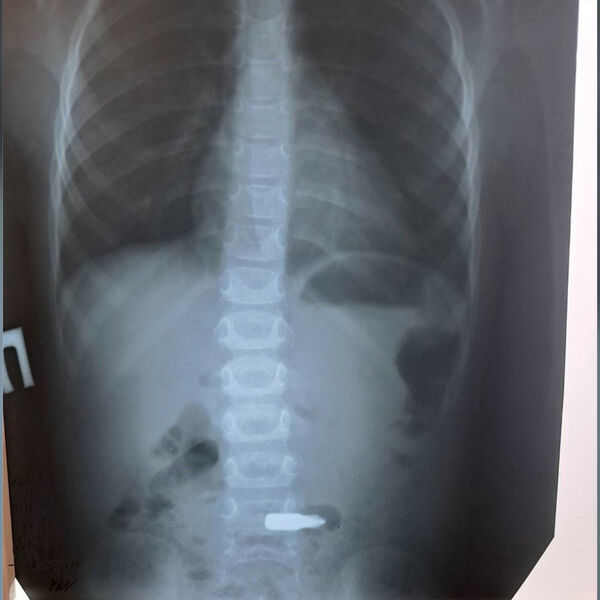

Медики Балаковской городской больницы спасли ребенка, который проглотил биту от шуруповерта. Об этом сообщает пресс-служба медицинского учреждения.

В больницу был доставлен четырехлетний мальчик с подозрением на инородное тело в желудке. Выяснилось, что мальчик проглотил деталь от шуруповерта. Врачи-эндоскописты извлекли биту от инструмента под общим наркозом.

Вмешательство прошло успешно, некоторое время мальчик находился под наблюдением врачей и был выписан на амбулаторное лечение.